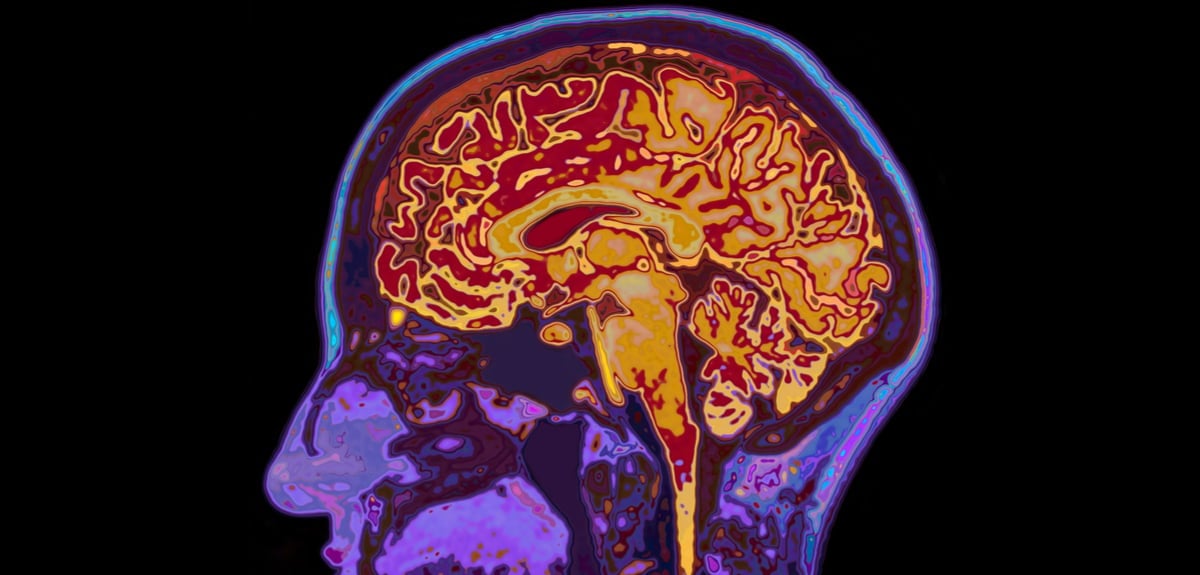

Τα πειράματα με εικονική πραγματικότητα αποκάλυψαν ότι ο εγκέφαλος δεν αποθηκεύει τις πληροφορίες με ενιαίο τρόπο αλλά ενεργοποιεί διαφορετικά βιολογικά προγράμματα, το καθένα με τον δικό του ρυθμό. Ο θάλαμος φαίνεται πως διαδραματίζει τον κρίσιμο ρόλο της επιλογής, καθώς διακρίνει ποιες εμπειρίες έχουν επαρκές βάρος ώστε να μεταφερθούν στον φλοιό, όπου οι νευρικές συνδέσεις ενισχύονται και η μνήμη αποκτά σταθερό θεμέλιο. Η σταδιακή αυτή πορεία στηρίζεται από τρία μόρια που καθορίζουν τη διάρκεια και την ανθεκτικότητα κάθε ανάμνησης.

Η εικόνα που προκύπτει ανατρέπει την παλαιότερη, απλουστευμένη άποψη για μια μνήμη που εγκαθίσταται μονομιάς και παραμένει αναλλοίωτη. Αντίθετα, η μνήμη παρουσιάζεται ως ένα ζωντανό οικοδόμημα που εξελίσσεται, μεταμορφώνεται και ενισχύεται με τον χρόνο. Η κατανόηση αυτού του μηχανισμού ανοίγει νέες προοπτικές για την έρευνα νευροεκφυλιστικών νόσων, όπου η διατήρηση των αναμνήσεων τίθεται στο επίκεντρο της ανθρώπινης αξιοπρέπειας. Πηγή: Unboxholics